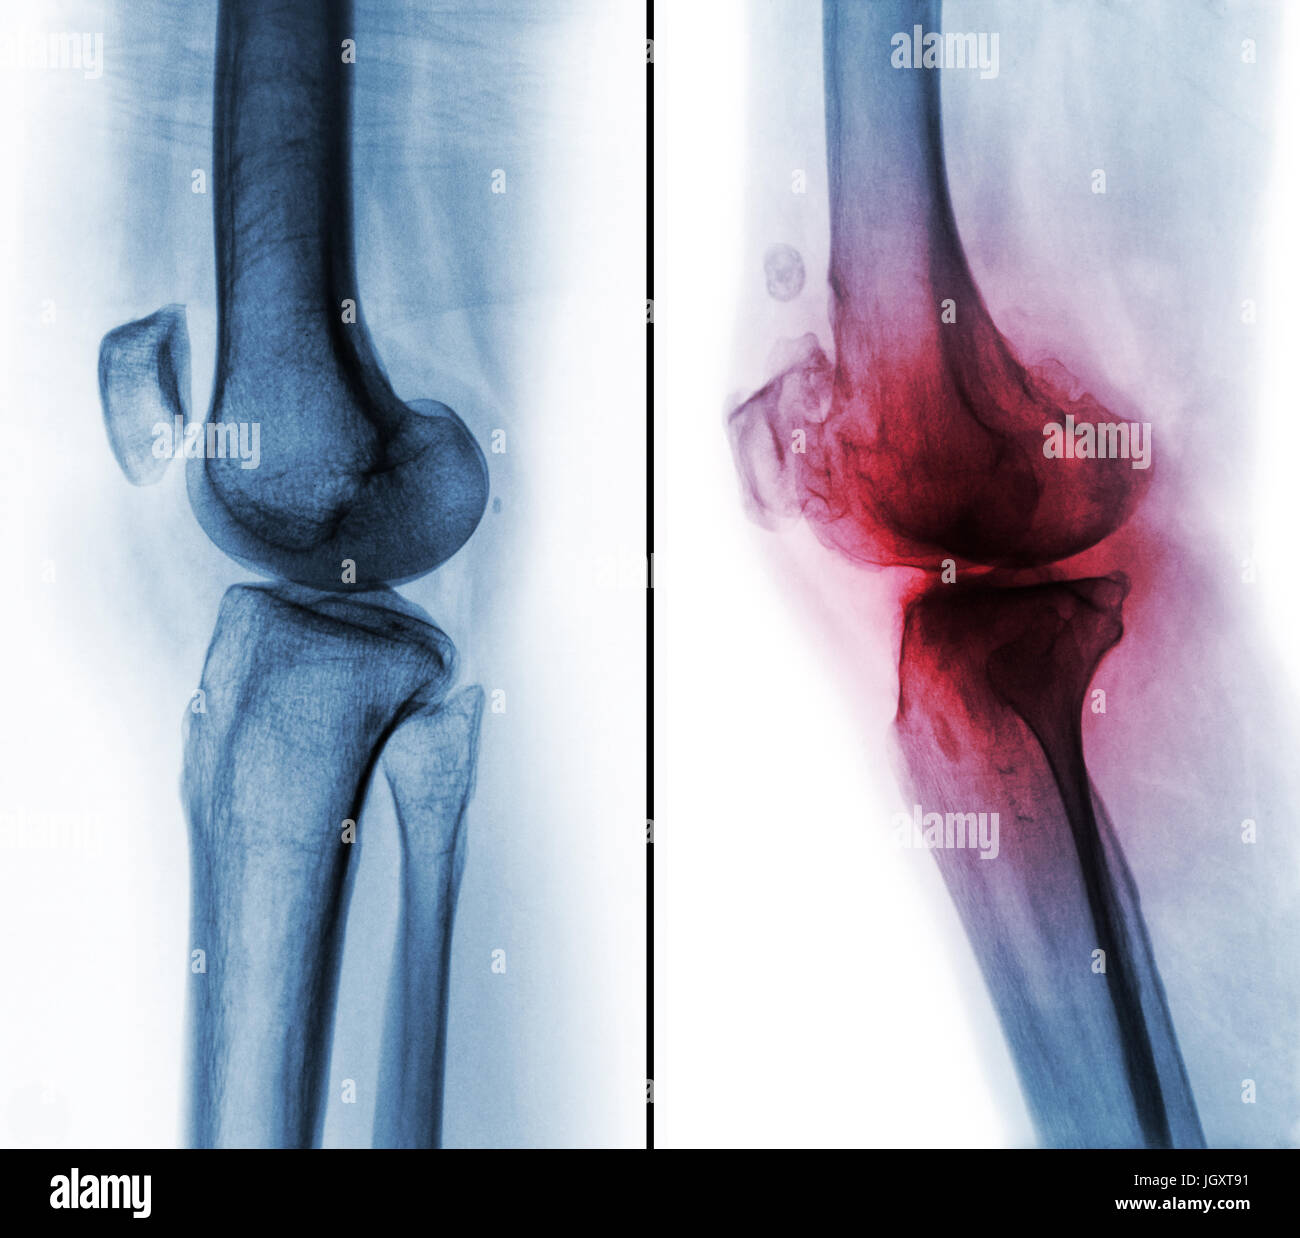

Comparaison entre le genou humain normal ( image de gauche ) et de l'arthrose du genou ( image de droite ) . Vue latérale . Banque D'Imageshttps://www.alamyimages.fr/image-license-details/?v=1https://www.alamyimages.fr/photo-image-comparaison-entre-le-genou-humain-normal-image-de-gauche-et-de-l-arthrose-du-genou-image-de-droite-vue-laterale-148107237.html

Comparaison entre le genou humain normal ( image de gauche ) et de l'arthrose du genou ( image de droite ) . Vue latérale . Banque D'Imageshttps://www.alamyimages.fr/image-license-details/?v=1https://www.alamyimages.fr/photo-image-comparaison-entre-le-genou-humain-normal-image-de-gauche-et-de-l-arthrose-du-genou-image-de-droite-vue-laterale-148107237.htmlRFJGXT85–Comparaison entre le genou humain normal ( image de gauche ) et de l'arthrose du genou ( image de droite ) . Vue latérale .

Comparaison entre le genou humain normal ( image de gauche ) et de l'arthrose du genou ( image de droite ) . Vue latérale . Banque D'Imageshttps://www.alamyimages.fr/image-license-details/?v=1https://www.alamyimages.fr/photo-image-comparaison-entre-le-genou-humain-normal-image-de-gauche-et-de-l-arthrose-du-genou-image-de-droite-vue-laterale-148107296.html

Comparaison entre le genou humain normal ( image de gauche ) et de l'arthrose du genou ( image de droite ) . Vue latérale . Banque D'Imageshttps://www.alamyimages.fr/image-license-details/?v=1https://www.alamyimages.fr/photo-image-comparaison-entre-le-genou-humain-normal-image-de-gauche-et-de-l-arthrose-du-genou-image-de-droite-vue-laterale-148107296.htmlRFJGXTA8–Comparaison entre le genou humain normal ( image de gauche ) et de l'arthrose du genou ( image de droite ) . Vue latérale .

Comparaison entre le genou humain normal ( image de gauche ) et de l'arthrose du genou ( image de droite ) . Vue latérale . Banque D'Imageshttps://www.alamyimages.fr/image-license-details/?v=1https://www.alamyimages.fr/photo-image-comparaison-entre-le-genou-humain-normal-image-de-gauche-et-de-l-arthrose-du-genou-image-de-droite-vue-laterale-148107261.html

Comparaison entre le genou humain normal ( image de gauche ) et de l'arthrose du genou ( image de droite ) . Vue latérale . Banque D'Imageshttps://www.alamyimages.fr/image-license-details/?v=1https://www.alamyimages.fr/photo-image-comparaison-entre-le-genou-humain-normal-image-de-gauche-et-de-l-arthrose-du-genou-image-de-droite-vue-laterale-148107261.htmlRFJGXT91–Comparaison entre le genou humain normal ( image de gauche ) et de l'arthrose du genou ( image de droite ) . Vue latérale .

Comparaison entre le genou humain normal ( image de gauche ) et de l'arthrose du genou ( image de droite ) . Vue latérale . Banque D'Imageshttps://www.alamyimages.fr/image-license-details/?v=1https://www.alamyimages.fr/photo-image-comparaison-entre-le-genou-humain-normal-image-de-gauche-et-de-l-arthrose-du-genou-image-de-droite-vue-laterale-148107279.html

Comparaison entre le genou humain normal ( image de gauche ) et de l'arthrose du genou ( image de droite ) . Vue latérale . Banque D'Imageshttps://www.alamyimages.fr/image-license-details/?v=1https://www.alamyimages.fr/photo-image-comparaison-entre-le-genou-humain-normal-image-de-gauche-et-de-l-arthrose-du-genou-image-de-droite-vue-laterale-148107279.htmlRFJGXT9K–Comparaison entre le genou humain normal ( image de gauche ) et de l'arthrose du genou ( image de droite ) . Vue latérale .